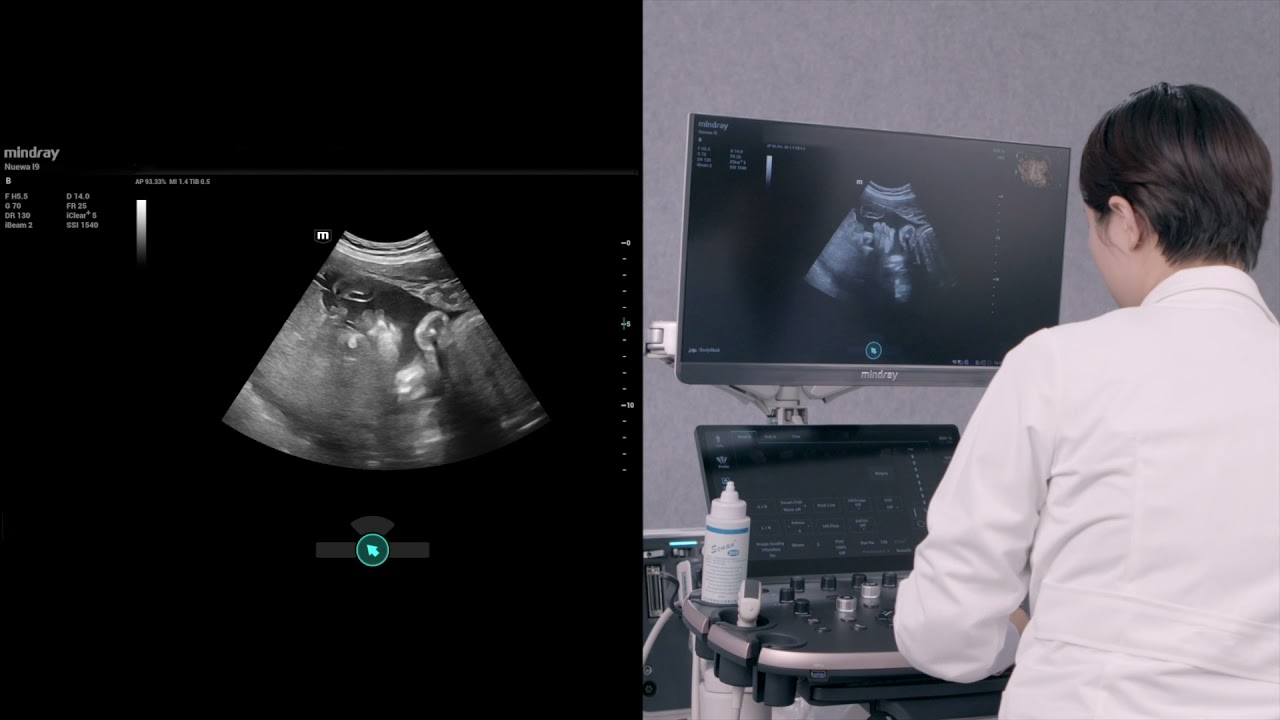

Algemene beeldvorming

Mindray Resona-oplossingen voor algemene beeldvorming helpen clinici bij het realiseren van nauwkeurigere en effici?ntere diagnose- en behandelingsresultaten door middel van sondes voor aparte toepassingen en effici?nte klinische toepassingstools.